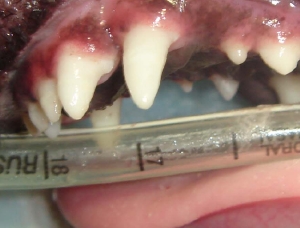

このように犬歯に対して広めに扇形の石灰を行います。

抜歯したら窩洞をスムーズにし何度も何度も肉芽を除去します。

縫合は緩めに、創面がかさなる部位で縫合します。

抗生剤ならびに鎮痛剤を処方し手術日から12日〜20日で抜糸(5分程度)となります。